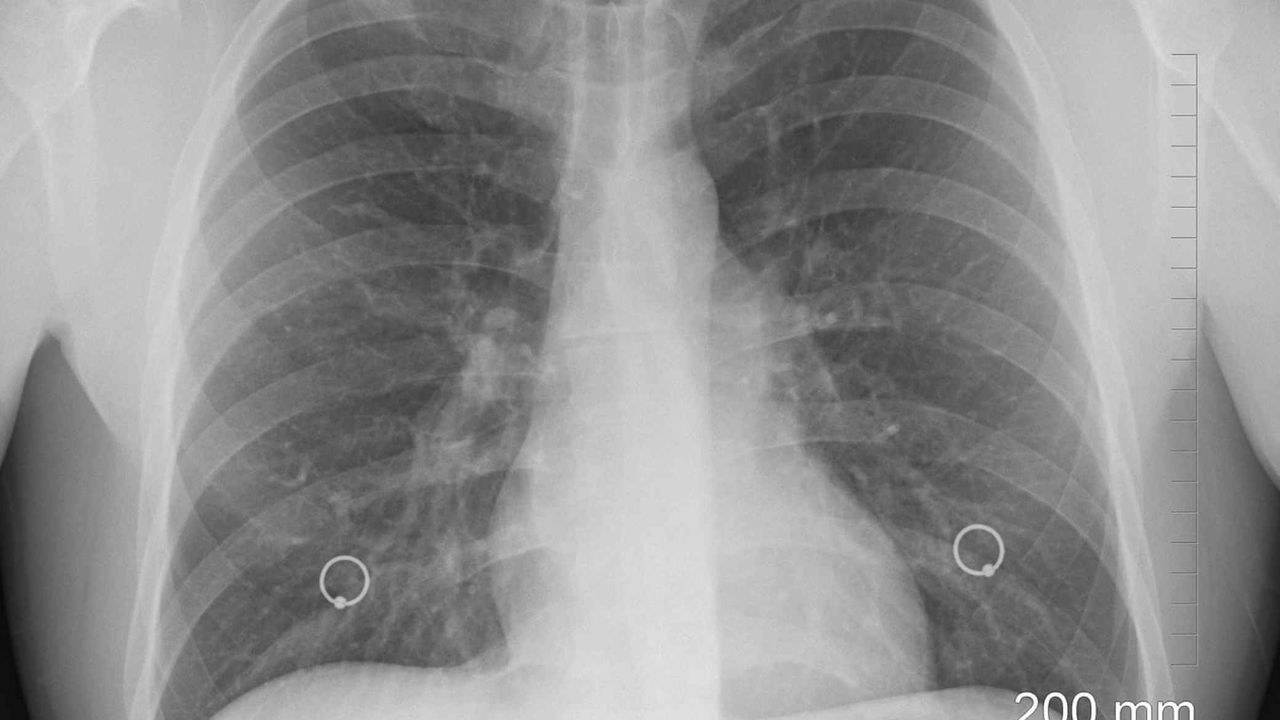

Sigaradan bağımsız olarak çevresel ve genetik etkenlerin de akciğer kanserine yol açabildiğini belirten Gündoğdu, ailede akciğer kanseri öyküsü, asbest ve radon gazına maruziyet, hava kirliliği gibi faktörlerin riski artırdığını söyledi. Hastalığın erken dönemde belirti vermediğine dikkat çeken Gündoğdu, "Geçmeyen öksürük, göğüs ağrısı, kanlı balgam, nefes darlığı gibi bulgular önemli. İleri evrede baş ağrısı, kemik ağrısı, iştahsızlık ve kilo kaybı da tabloya eklenebilir" diyerek erken tanının hayat kurtardığını ifade etti.